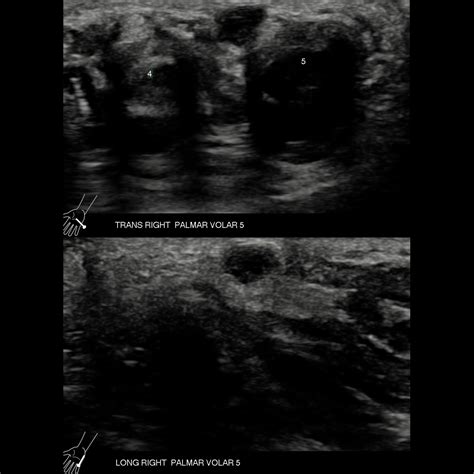

When you visit a doctor regarding a ganglion cyst palm of hand, they will likely perform a physical examination. They may use a technique called transillumination, where a small light is shone through the cyst; because these cysts are filled with clear fluid, they will often glow, confirming that they are not solid tumors.

In some cases, the physician may order imaging tests, such as:

• Ultrasound: To determine if the mass is fluid-filled or solid.

• X-rays: To rule out bone-related issues or underlying arthritis.

• MRI: Occasionally used to see smaller cysts that are hidden deep within the palm.